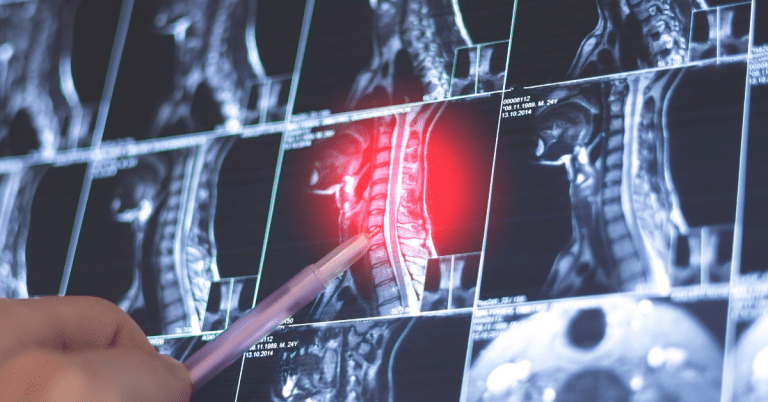

HealthOST 是 Nanox.AI 的高级骨骼解决方案,它分析常规 CT 扫描以评估椎体高度丢失和骨密度。在 2022 年 4 月获得 FDA 510(k) 批准的基础上,HealthOST 利用 AI 从 CT 扫描中提供脊柱的定性和定量分析,以支持临床医生评估和评估脊柱的肌肉骨骼疾病,如骨质疏松症,这种疾病可能在导致生活改变的骨折发生之前未被诊断。

由于脊柱评估软件分析的 CT 扫描是为了其他临床指征进行的,因此不需要额外的成像、辐射或患者时间,使其成为一种具有成本效益的筛查工具。HealthOST 无缝集成到现有的影像存储和通信系统(PACS)中,能够实现及时且适当的预防性护理。